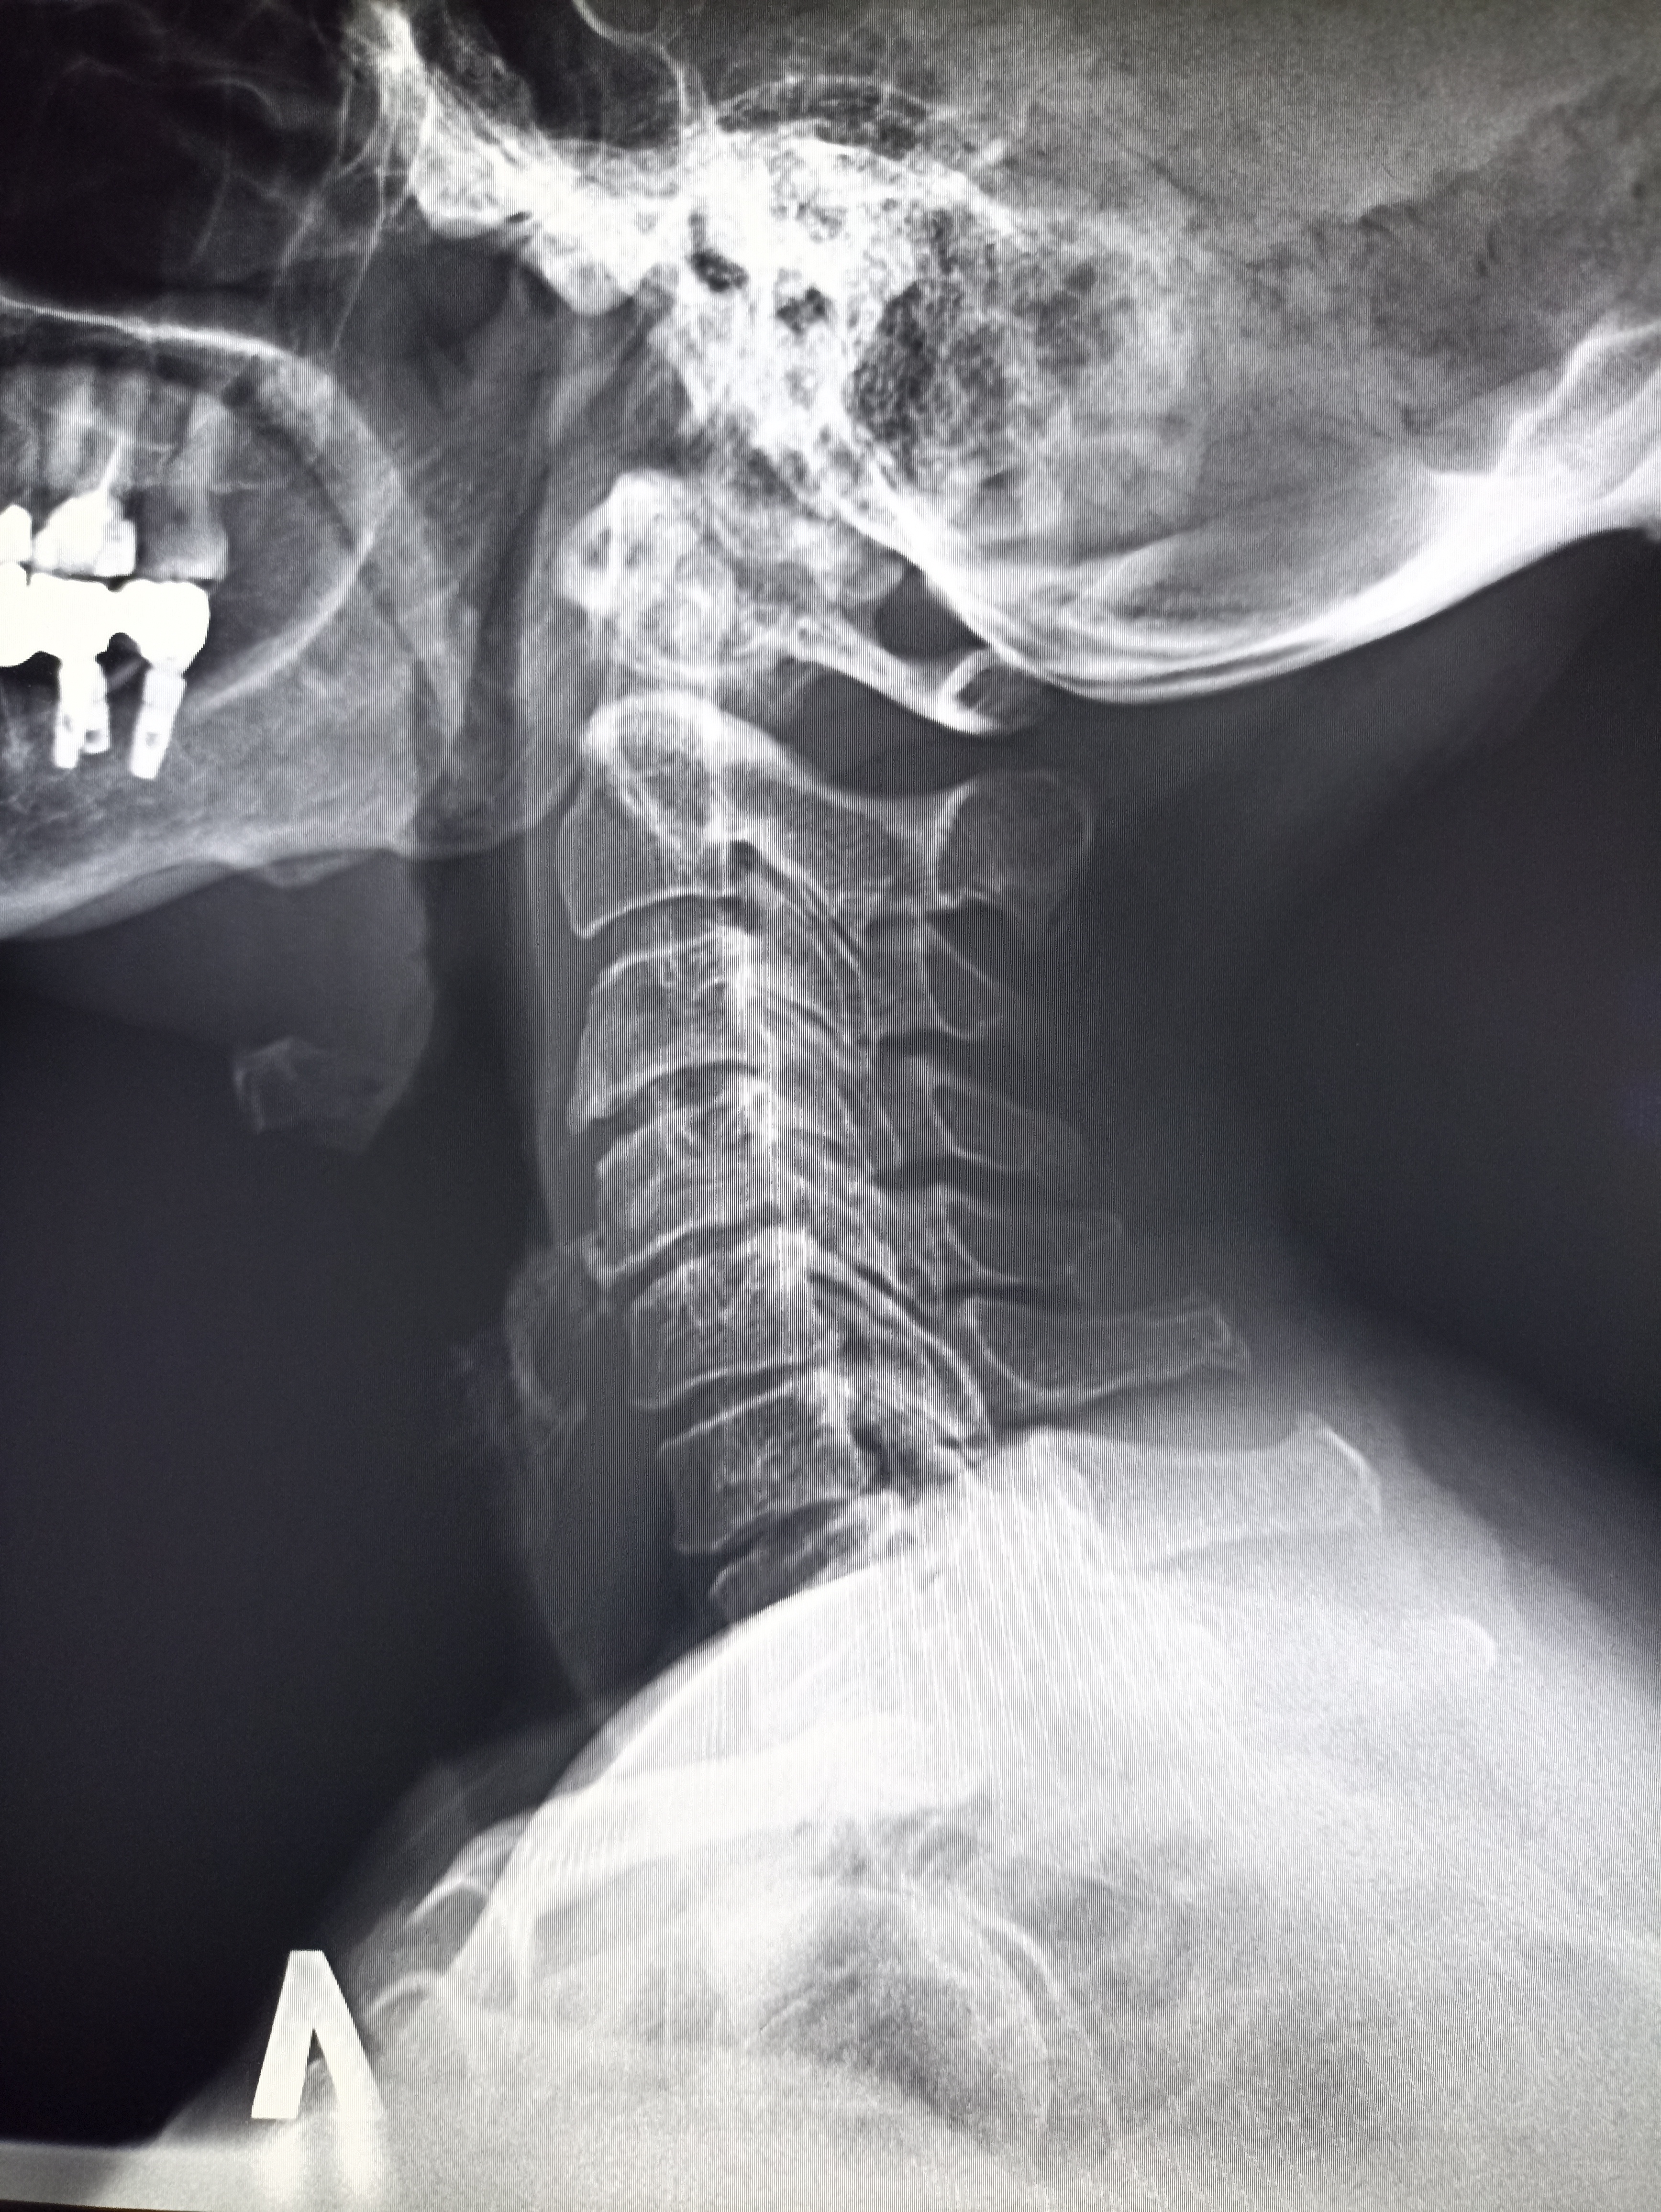

Никогда такой хуйни не было! И вот опять! Здравствуй двачик! Я итт буду с вами играть в рентгенолога, флексить зарплатой 31 к за октябрь и общатся! Давайте дружить! Угадывайте пиздецомы по фоточке и общайтесь ибо я тут чо-то заебалс. Штош погнали!